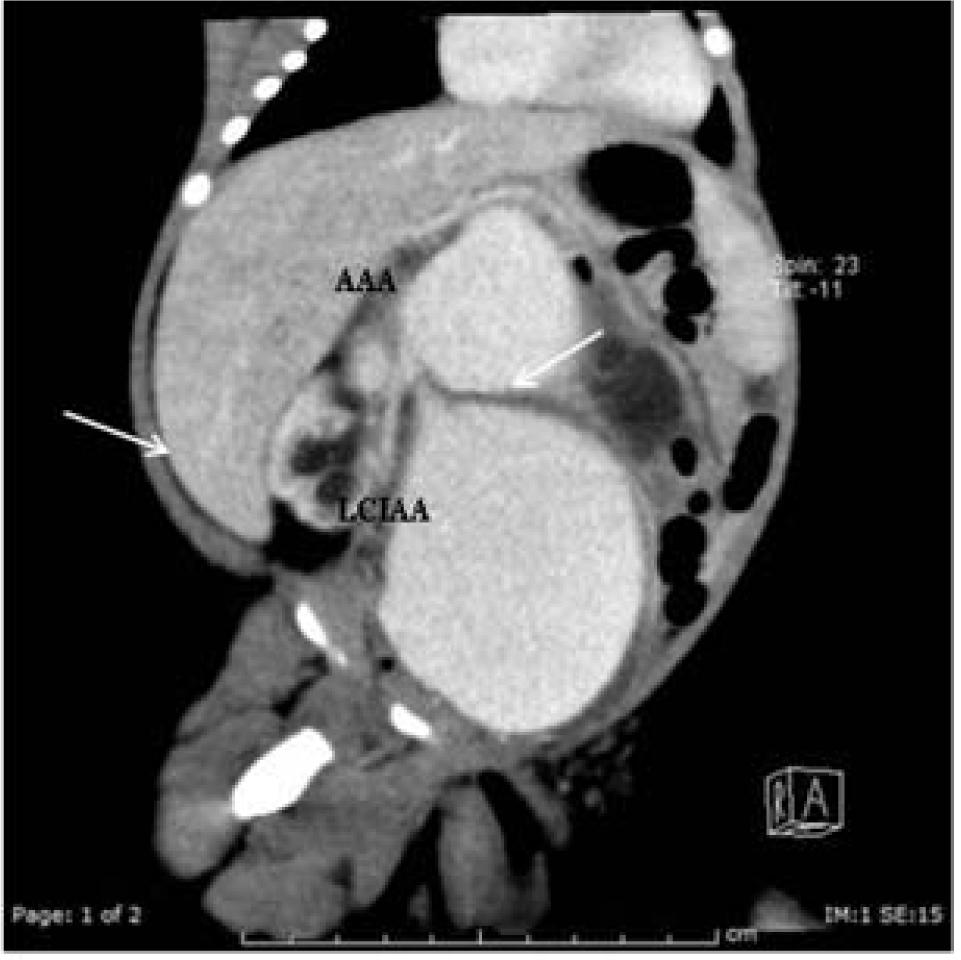

Figure 1